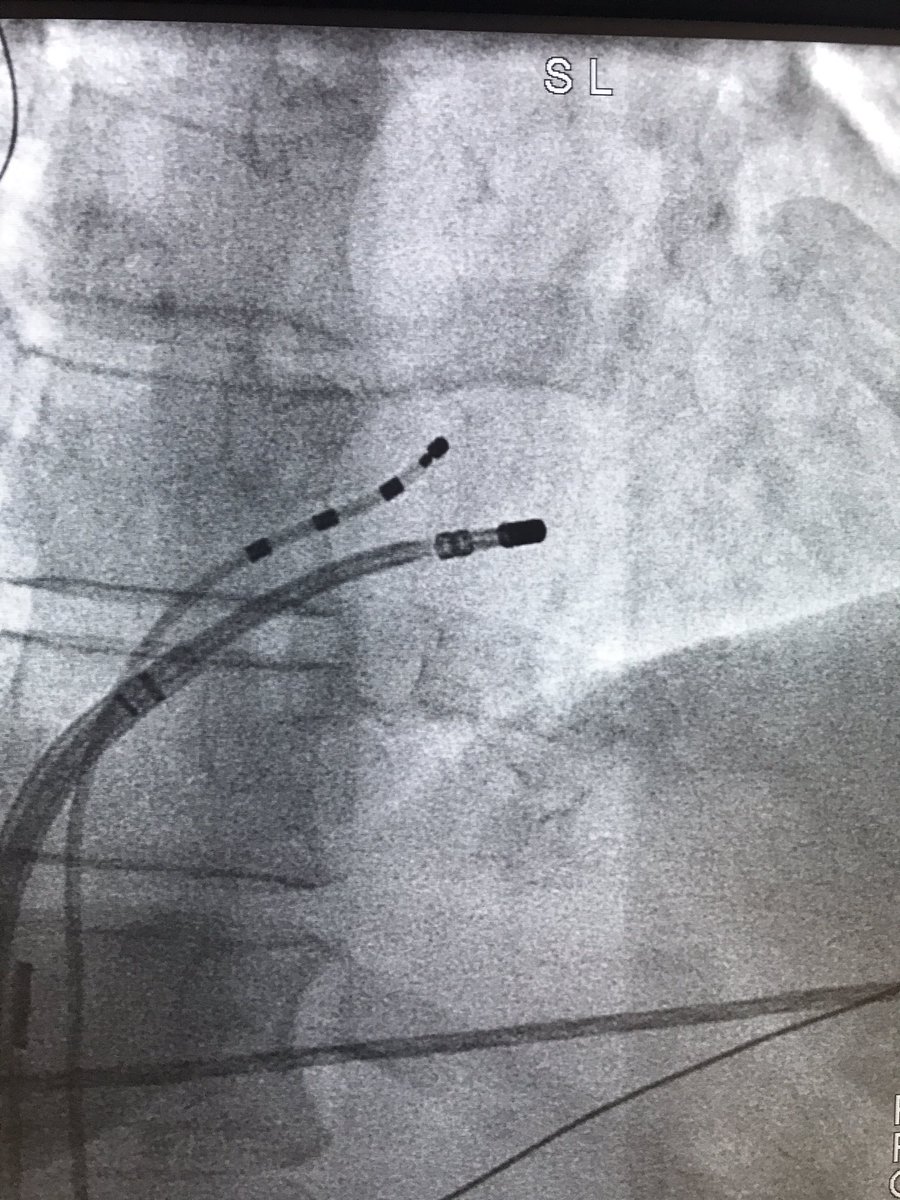

@1drhani

Mohammed Djelmami-Hani, MD, FHRS

7 years

When you start having PVCs while ablating one. Para Hisian PVC! Do or die shot! Single burn...done! Happy Thanksgiving #pvc #Thanksgiving